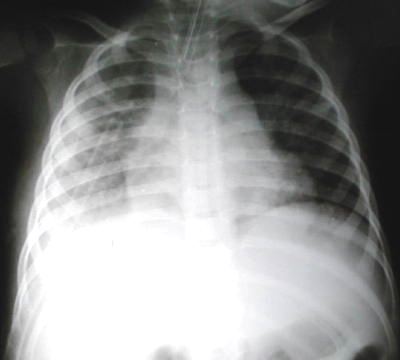

Radiología del tórax

• Rx. tórax PA (izquierda): Observamos lesion quística en base pulmonar derecho, aumento del volumen pulmonar a predominio basal derecho con mayor transparencia o halo periferico en relacion a neumotorax, liquido plaural, areas neumonicas con broncograma aereo mas acentuado enel lado derecho. el drenaje pleural o tubo de torax, cateter de PVC en cava superior y tubo endotraqueal.